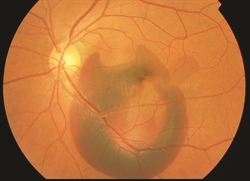

- Shares some clinical features with wet age-related macular degeneration The abnormal vessels in PCV cause vision loss when they leak fluid or blood into or under the retina (Figure 1). The abnormal vessels in PCV may also cause scarring or loss (sometimes called atrophy) of retinal tissue. Although PCV appears to affect only one eye in some patients, it often goes on to affect both eyes over time, so frequent monitoring is important.